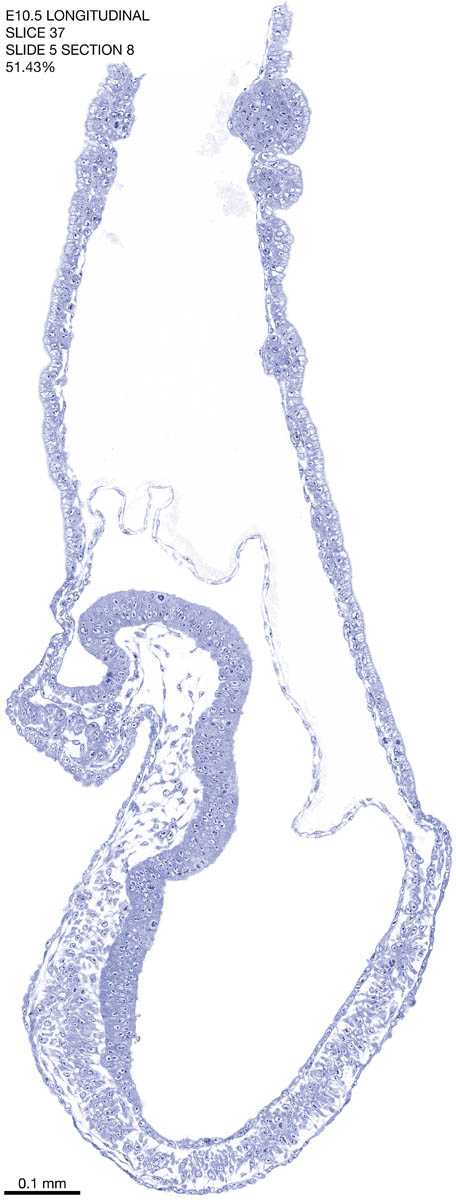

E10.5 Longitudianal Archive This page contains jpg files of ALL SLICES (each 3µm thick) that were scanned of the E10.5 longitudinally cut specimen. Download: Large | High Res Download: Large | High Res Download: Large | High Res Download: Large | High Res Download: Large | High Res Download: Large | High Res Download: Large | High Res Download: Large | High Res Download: Large | High Res Download: Large | High Res Download: Large | High Res Download: Large | High Res Download: Large | High Res Download: Large | High Res Download: Large | High Res Download: Large | High Res Download: Large | High Res Download: Large | High Res Download: Large | High Res Download: Large | High Res Download: Large | High Res Download: Large | High Res Download: Large | High Res Download: Large | High Res Download: Large | High Res Download: Large | High Res Download: Large | High Res Download: Large | High Res Download: Large | High Res Download: Large | High Res Download: Large | High Res Download: Large | High Res Download: Large | High Res Download: Large | High Res Download: Large | High Res Download: Large | High Res Download: Large | High Res Download: Large | High Res Download: Large | High Res Download: Large | High Res Download: Large | High Res Download: Large | High Res Download: Large | High Res Download: Large | High Res Download: Large | High Res Download: Large | High Res Download: Large | High Res Download: Large | High Res Download: Large | High Res Download: Large | High Res Download: Large | High Res Download: Large | High Res Download: Large | High Res Download: Large | High Res Download: Large | High Res Download: Large | High Res Download: Large | High Res Download: Large | High Res